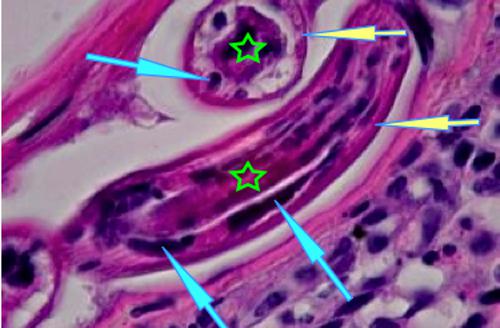

Dans le derme, on note des lésions très exsudatives et inflammatoires centrées sur les annexes folliculaires et sudorales. Il s’agit de remaniements inflammatoires à forte prédominance éosinophile avec en général obstruction des lumières annexielles par l’infiltrat (Photo 13,14,15). Ici et là, sur certaines coupes, notamment sur la réaction au PAS, on observe de petits éléments vermiformes, ronds, cylindriques non segmentés, à cuticule lisse, intraluminaux ou intra-pariétaux au sein des follicules pileux (Photo 16,17,18,19,20,21,22,23) ou des glandes sudorales apocrines épitrichiales (Photo 24 & 25), évoquant des helminthes.

Photo 18 (Hémalun Eosine X 200) peau velue : Certains éléments vermiformes sont

inclus dans de petites logettes au sein de la paroi des follicules pileux,

ici un même élément vermiforme en coupe transversale et longitudinale.

Légendes de la Photo 18 :

- Étoile rouge : lumière du follicule pileux

- Double flèche verte : GEE

- Double flèche bleue : derme inflammatoire péri-folliculaire (infiltrat riche en granulocytes éosinophiles et en palsmocytes)

- Flèches jaunes : élément vermiforme rond cylindrique non segmenté

Photo 19 (Hémalun Eosine X 400) peau velue : Vue rapprochée de la Photo 18.

Ici un même élément vermiforme en coupe transversale et longitudinale :

élément rond cylindrique non segmenté à cuticule lisse et fine.

Il semble y avoir des cellules musculaires et une cavité centrale contenant des organes.

Légendes de la Photo 19 :

- Étoile verte : “matériel organique” dans la cavité centrale

- Flèches turquoises : cellules musculaires sous-cuticulaires

- Flèches jaunes : cuticule du ver